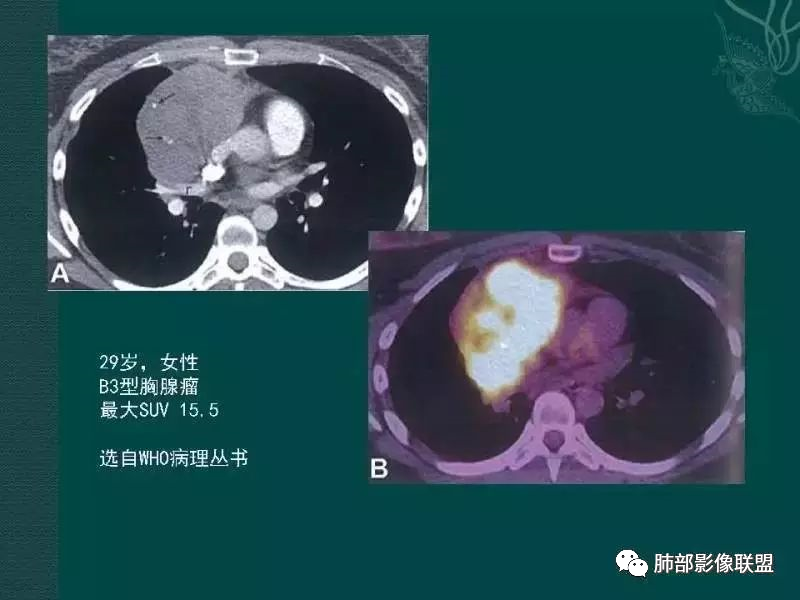

1、临床特点:47岁男性,咳嗽咳痰1年余。实验室检查无特殊。

2、影像特点:前纵隔偏左侧软组织影,密度相对均匀,未见明显包膜钙化及实质内钙化,局部边缘浅分叶,周围脂肪间隙密度增高、浑浊,未见侵犯大血管、未见纵隔内淋巴结转移、未见侵犯心包内结构、未见胸膜转移结节、未见肿块沿着纵隔胸膜蔓延,未见胸腔积液。增强后动脉期不均匀强化,未见明显纤维分隔。

3、 病 例 小 结:40岁以上,前纵隔偏侧性生长的肿块,常规考虑胸腺瘤。难点就在于胸腺瘤的分型。但是对于前纵隔占位影像诊断的关键在于区分胸腺囊肿、胸腺瘤、胸腺癌及其他恶性肿瘤。至于胸腺瘤,主要在于判断有无侵袭性。